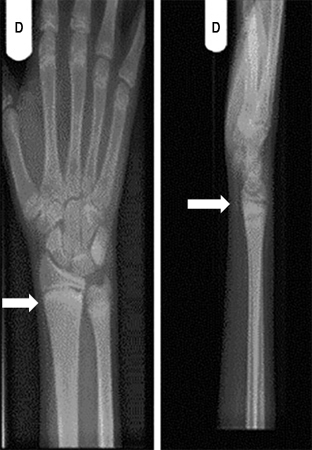

Punho direito de um paciente com raquitismo por deficiência de vitamina D antes do tratamento. Sua radiografia do punho direito revelou placas finais escleróticas e aumentadas do rádio e ulna (setas)

Seerat I, Greenberg M. Hypocalcaemic fit in an adolescent boy with undiagnosed rickets. BMJ Case Reports 2010; doi:10.1136/bcr.10.1136/bcr10.2008.1153